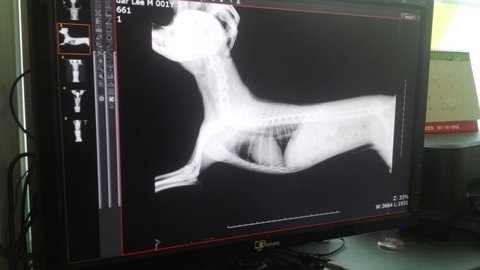

달이가 바늘을 먹다는 소식에 부랴부랴 동물병원에서 엑스레이를 찍었는데

다행히 안 먹은 것으로 판명났어요.